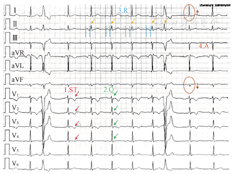

例3:见图4。按照STQRA心电图分析方法,首先分析ST(ST段及T波),可见Ⅱ、Ⅲ、aVF导联ST段压低,aVR导联ST段抬高、T波倒置,基本除外急性ST段抬高型心肌梗死。分析完ST之后,分析Q(QRS波群),可见QRS波群增宽,时限169 ms,V1、V2导联呈"M型",V5、V6导联为Rs波,且s波宽阔、粗钝,考虑为完全性右束支传导阻滞,但胸前导联无继发性ST-T改变,V1、V2导联T波正向,胸前导联QRS波群递增不良,结合下壁导联ST段压低,不排除前壁心肌梗死可能。此外,QRS波群振幅普遍减低,符合QRS低电压。第3步,分析R(心率和节律),可见心室率67次/min,在正常范围;心脏节律规整,P波规律出现,形态恒定,在Ⅰ、Ⅱ、aVF、V3~V6导联直立,aVR导联倒置,为窦性P波;再分析P波与QRS波的关系可以发现P波与QRS波群没有固定关系且心房率大于心室率,为三度房室传导阻滞。最后分析A(电轴),可见Ⅰ导联QRS波群振幅代数和为负,aVF导联QRS波群振幅代数和为正,心电轴落在第三象限,范围在+90°~+180°之间,为电轴右偏,也可以进一步精确计算角度。按照计算方法,计算出QRS电轴为+102°,达到左后分支阻滞标准。故此份心电图的诊断为:(1)窦性心律;(2)前壁心肌梗死?;(3)三度房室传导阻滞;(4)完全性右束支传导阻滞;(5)电轴右偏。此例患者因为存在QRS低电压、陈旧性心肌梗死图形、多种传导阻滞,因此临床应高度怀疑浸润性心肌病。